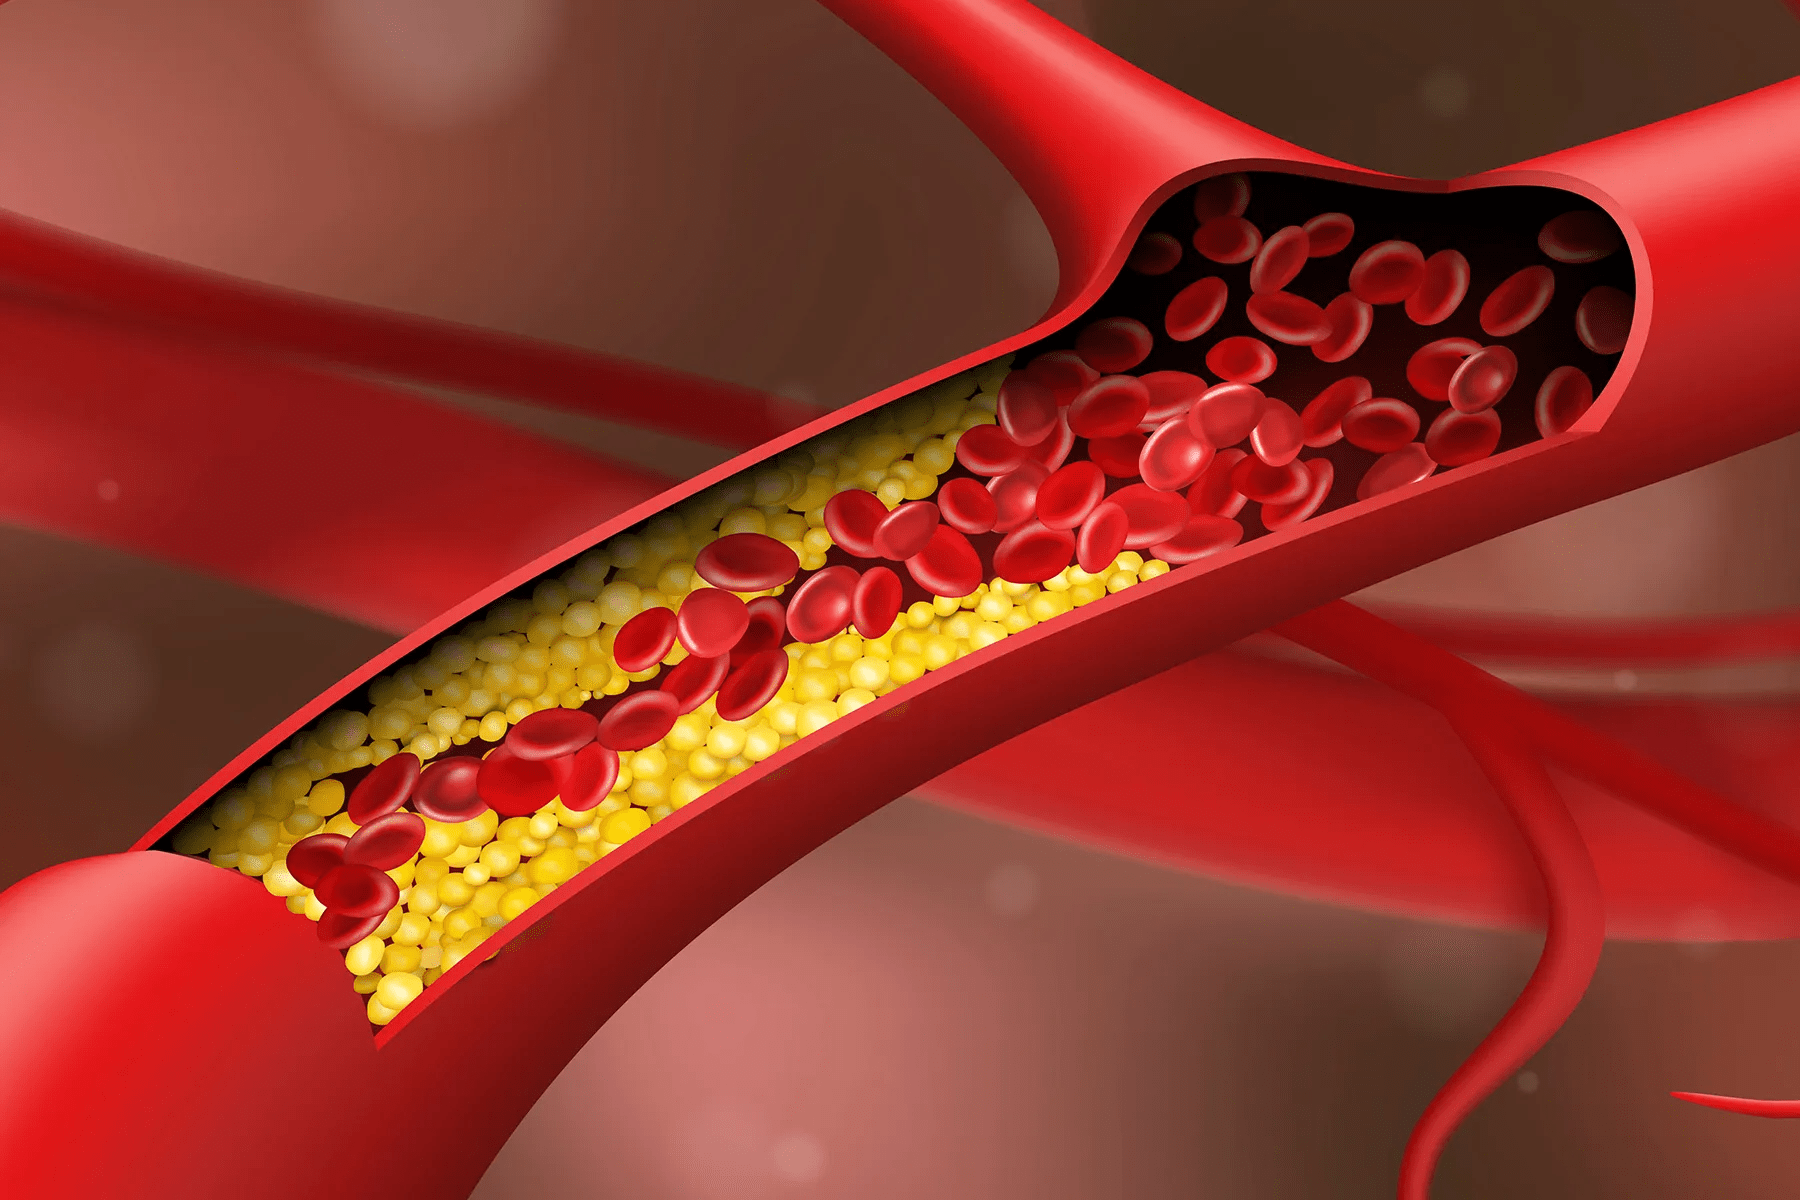

Artery blockages don’t appear overnight. They build slowly, quietly, and often without pain. That’s why many adults go years without realizing their arteries may be narrowing. The danger comes when cholesterol, inflammation, or plaque reduces blood flow.

When arteries narrow, blood has a harder time reaching your extremities. You might feel chilly fingers, tingling toes, or a persistent coolness that feels out of place. Many seniors think this is normal aging. But researchers suggest poor circulation may play a role.

5. Shortness of Breath During Simple Tasks

Poor circulation may delay wound healing. Something as small as a nick from trimming your nails can take surprisingly long to close. That slow process might reflect reduced blood flow to the skin.

It can feel like a quick head rush—standing too fast, turning too quickly. But recurring dizziness may occur when blood flow to the brain briefly dips. Many blame dehydration or skipped meals, but your arteries may be trying to get your attention.

2. Swelling in Your Ankles or Feet